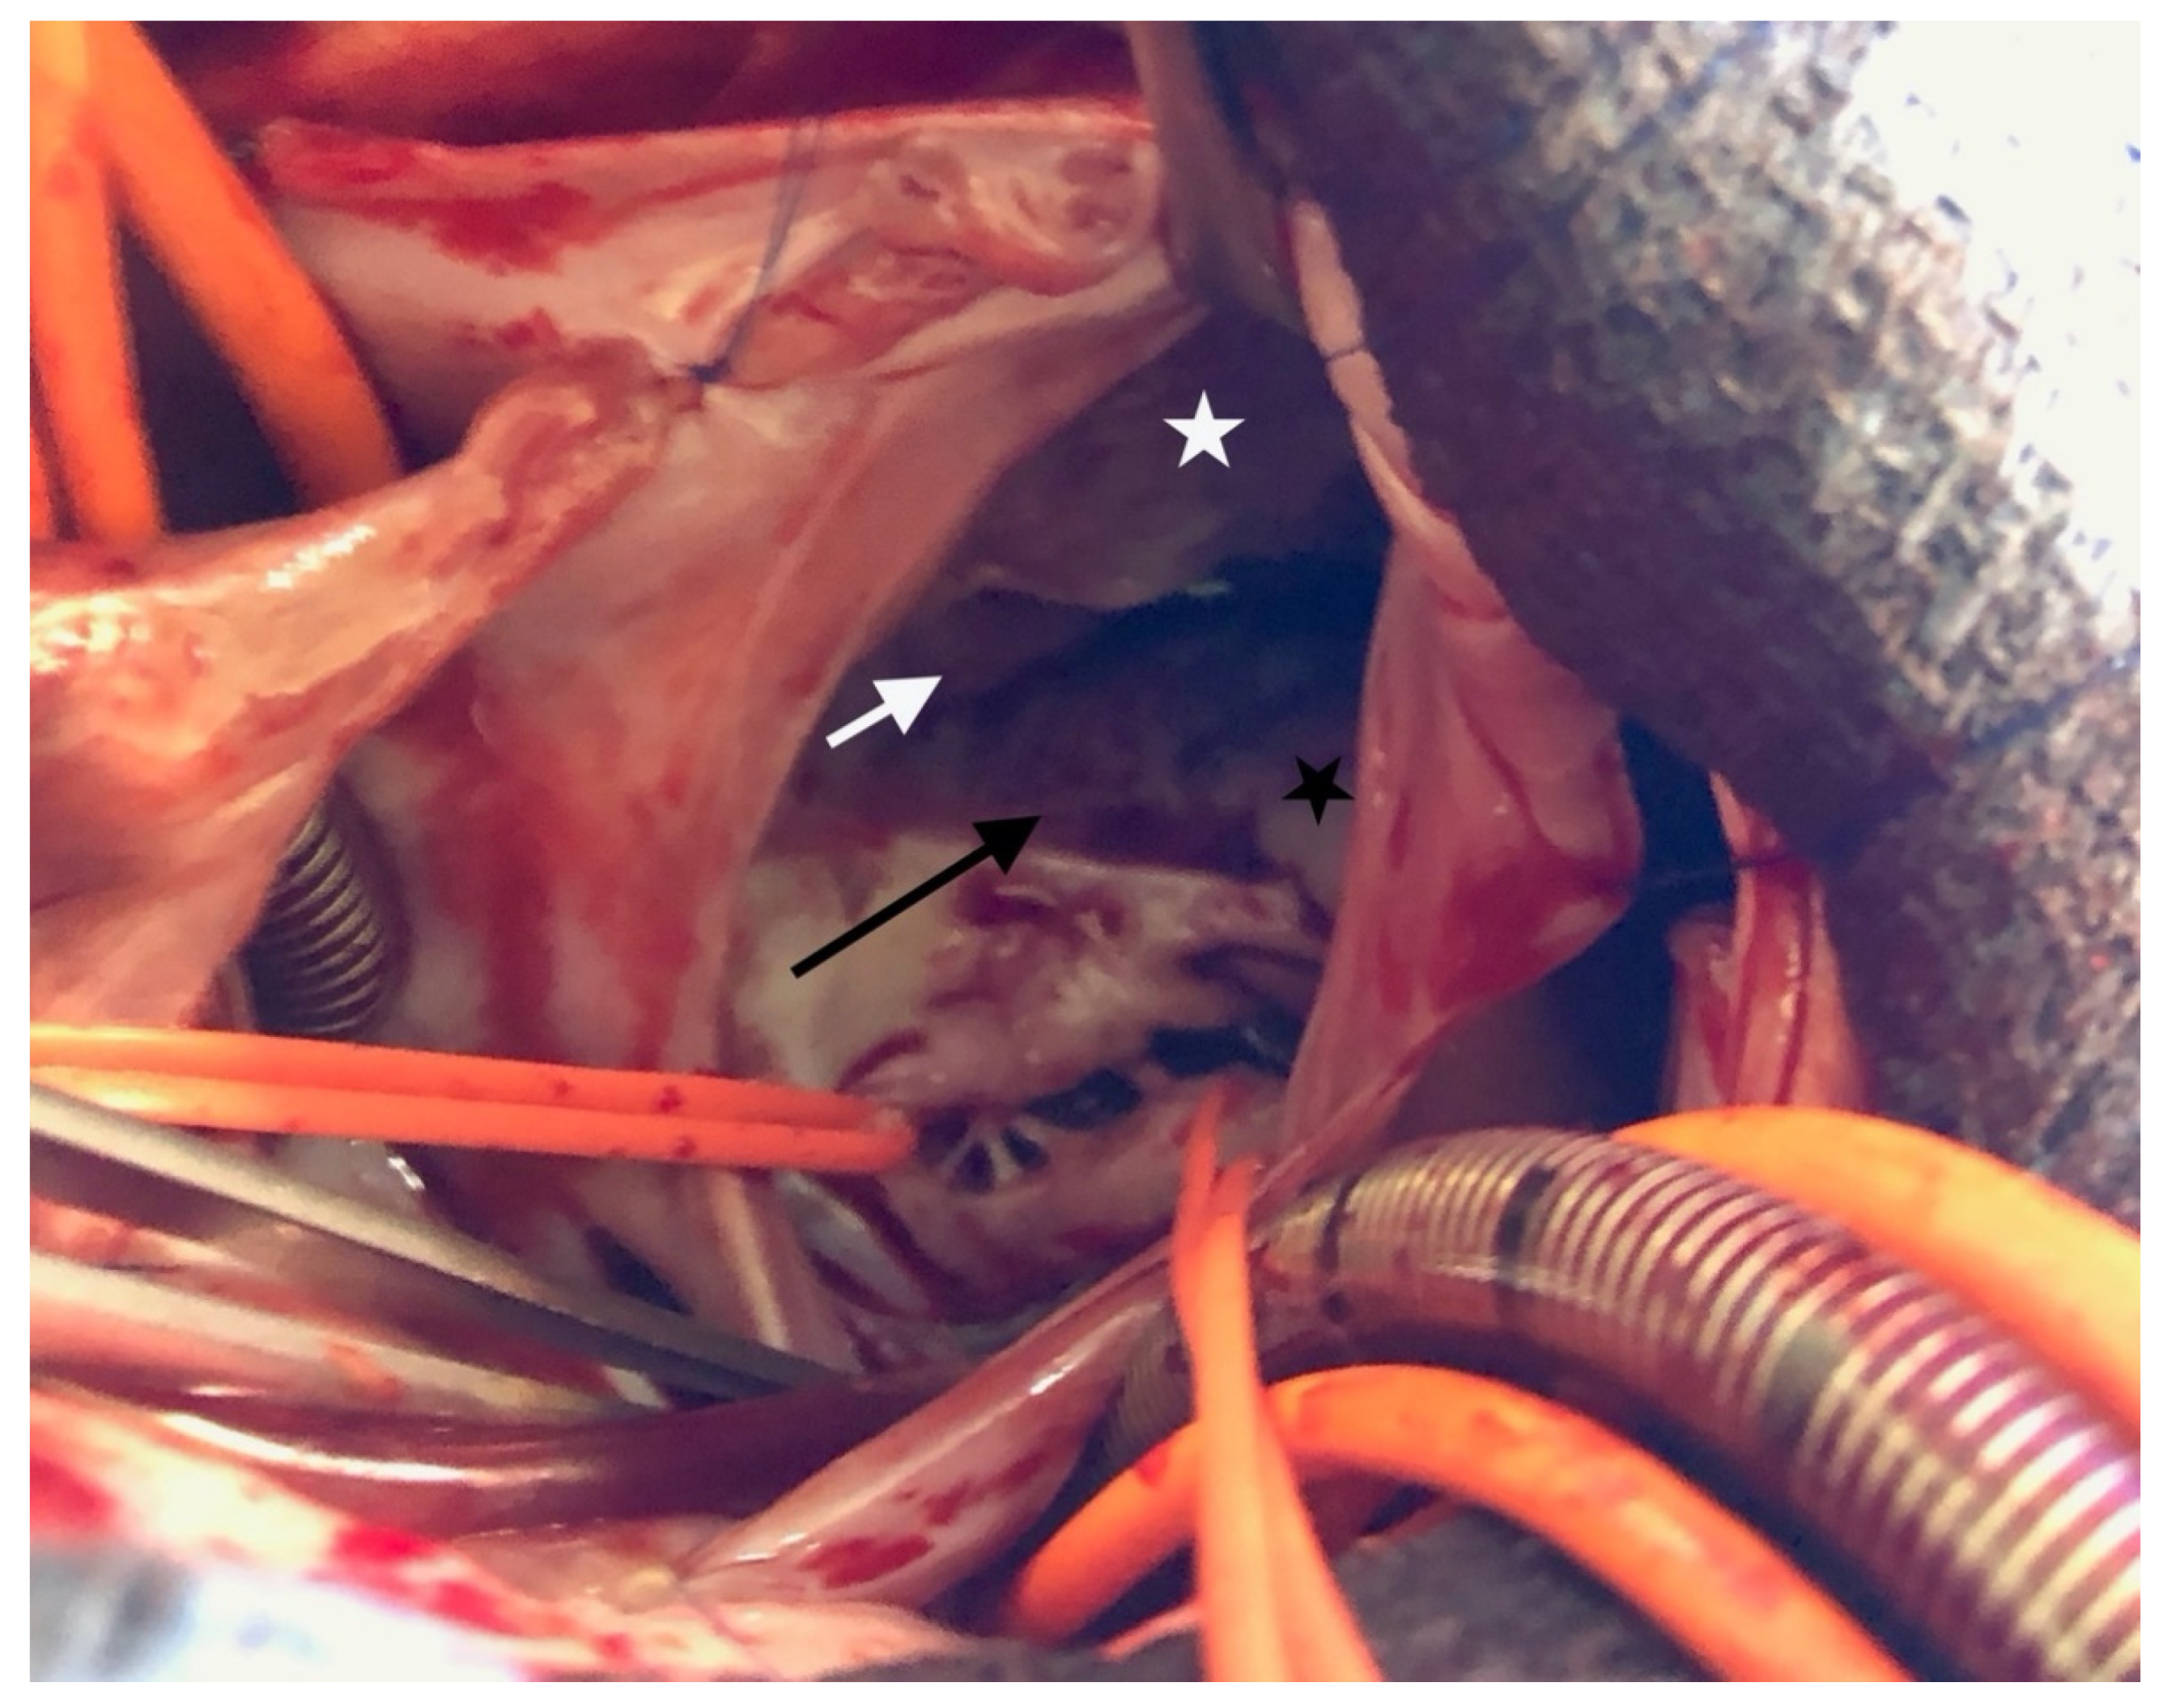

Partial AVCD was also indisputable with respect to the left side. There was no ventricular septal defect, and the left atrioventricular annulus was complete and glued to the septal crest. There were three components: one anterior, one posterior and one mural valve (Figure 4). The cleft was not complete; a few mm of tissue united the anterior and posterior components paraseptally. There was a typical ostium primum. Thus, the procedure consisted of a tricuspid “cone” repair with the complete closure of the ostium primum ASD via an autologous pericardial patch and the closure of the left atrioventricular cleft.

Figure 4. The left atrioventricular valve is composed of 3 leaflets. A: anterior bridging leaflet; P: posterior bridging leaflet; arrow: incomplete cleft; asterisk: left mural leaflet.